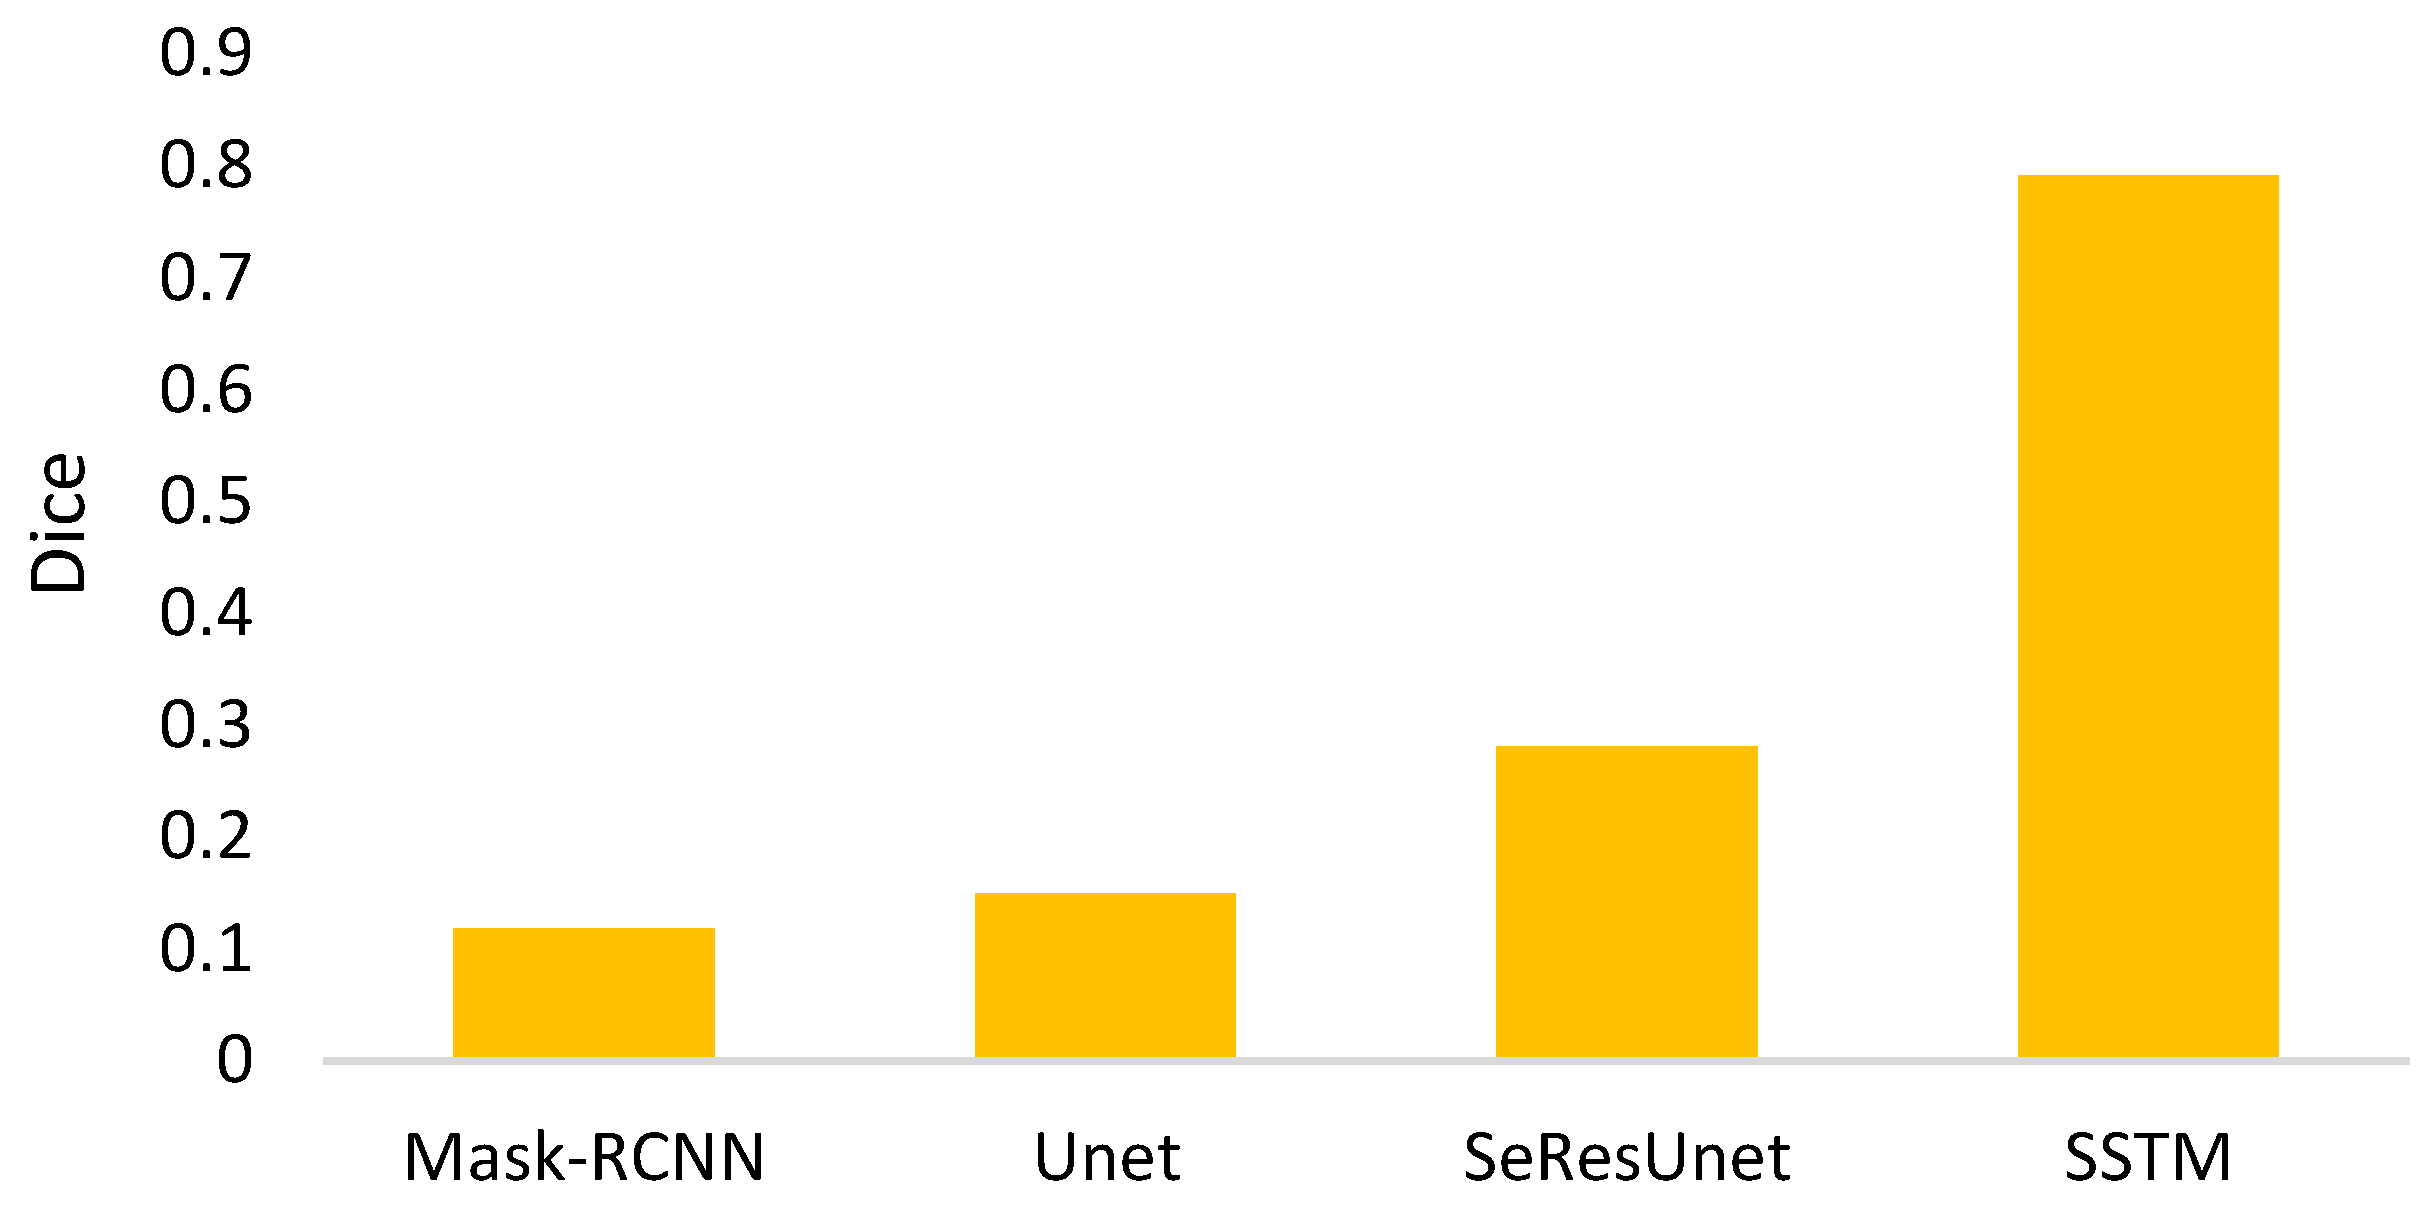

- The goal of semi-automated segmentation is to provide the doctors with an efficient and effective tool for marking the nodules. Actually, most existing marking systems perform the fully automated segmentation as an initial mark. Then, it is revised by the doctor. Hence, a potential question for effectiveness differences of the proposed semi-automated segmentation and fully automated ones needs to be replied. For this question, three recent fully automated segmentation methods, including Mask-RCNN [7], Unet [24], and SeResUnet [34] were compared with the proposed method SSTM. Figure 20 reveals that the proposed SSTM achieves much better dice than the fully automated methods, reaching a dice improvement of 392.3%. The first potential reason is that the training data for the compared methods are not enough. Second, additional click information is very helpful to segmentation. In summary, this result says that the proposed idea is robust if facing small data. Moreover, it is easy and cheap. Note that all methods were executed with the same experimental settings.